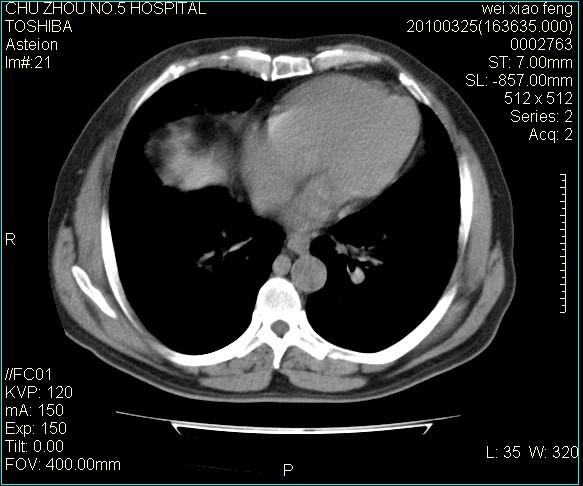

男,60岁,反复咳、痰、喘3月,加重3天。

间质性肺炎伴间质纤维化!不排除伴有职业病!

考虑间质性肺炎伴间质纤维化。

间质病变,间质炎症,间质纤维化趋势